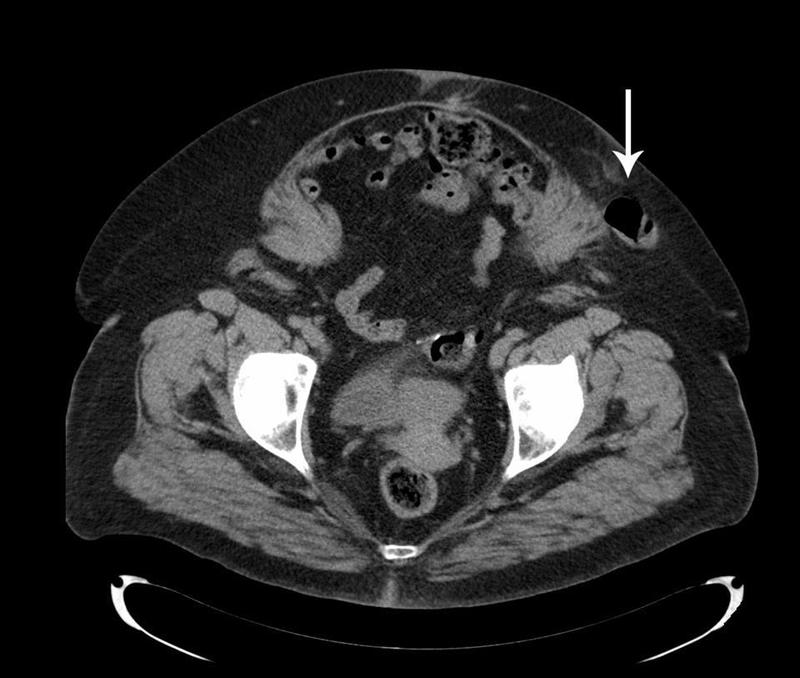

volte delle dimensioni cospicue. Il nome di un’ernia deriva dalla sede anatomica dove si forma (inguinale, crurale, laparocele o ernia su cicatrice chirurgica). La pressione aumentata spinge i visceri addominali verso l’esterno provocando l’aumento di dimensioni dell’ernia stessa ed il suo possibile incarceramento (impossibilità di riportare l’ernia in addome ). Non ci sono “cinti “ che tengano perché questa pressione raggiunge picchi veramente alti.

La pressione all’interno dell’addome schiaccia le grosse vene che sono al suo interno (vena cava inferiore e vene iliache, la cui pressione è di soli pochi mm. di mercurio ). Il sangue che tornando dagli arti verso il cuore deve passare attraverso queste vene, viene bloccato per lo schiacciamento di queste e trasmette la pressione dell’addome a tutte le altre vene a valle. Questa pressione aumenta nei soggetti con varici il reflusso di sangue e l’aggravamento delle varici stesse.